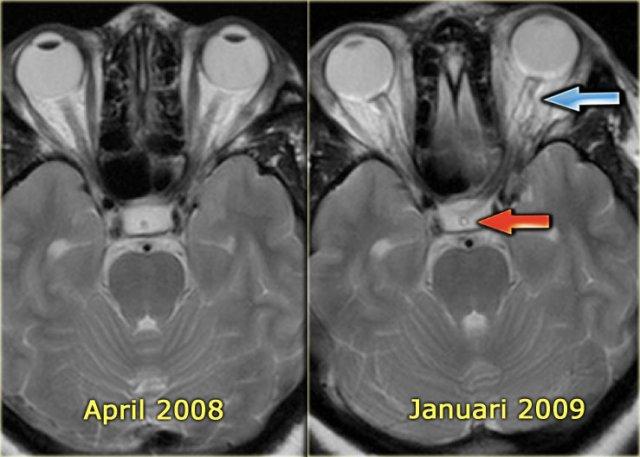

Huyết khối xoang màng cứng mạn tính và các hội chứng liên quan

Thông động tĩnh mạch màng cứng (DAVF)

Huyết khối xoang màng cứng mạn tính có thể dẫn đến hình thành thông động tĩnh mạch màng cứng và tăng áp lực dịch não tủy.

DAVF (thông động tĩnh mạch màng cứng) là sự kết nối bất thường giữa các động mạch màng cứng – vốn là các nhánh của động mạch cảnh ngoài – với các xoang tĩnh mạch.

Huyết khối xoang được ghi nhận ở nhiều bệnh nhân có thông động tĩnh mạch màng cứng, tuy nhiên cơ chế bệnh sinh vẫn chưa được làm rõ (10).

Có hai cơ chế có thể xảy ra: (a) viêm tắc tĩnh mạch huyết khối của xoang màng cứng có thể gây ra thông động tĩnh mạch màng cứng, và (b) trong quá trình tiến triển của thông động tĩnh mạch màng cứng, hiện tượng đảo ngược dòng chảy có thể dẫn đến huyết khối.

Các phân loại DAVF hiện hành chủ yếu tập trung vào sự hiện diện của trào ngược màng mềm liên quan đến tăng áp tĩnh mạch não, dẫn đến nhồi máu tĩnh mạch não hoặc xuất huyết.

Hình ảnh chụp mạch số hóa xóa nền (DSA) bên trái của một bệnh nhân có DAVF.

Lưu ý sự thông thương trực tiếp giữa các nhánh của động mạch cảnh ngoài và xoang ngang (mũi tên xanh).

Tiếp tục xem các hình ảnh chuỗi xung T2W.

Hình ảnh chuỗi xung T2W bên trái trong quá trình theo dõi.

Tháng 4 năm 2008 không ghi nhận bất thường.

Tháng 1 năm 2009 xuất hiện các dấu hiệu của tăng áp lực nội sọ như dịch não tủy bao quanh dây thần kinh thị giác và dịch não tủy trong cuống tuyến yên.

Huyết khối và tăng áp lực dịch não tủy

Ở một số bệnh nhân, huyết khối xoang màng cứng có thể dẫn đến rối loạn tuần hoàn tĩnh mạch kéo dài, ngay cả sau khi đã tái thông.

Tình trạng này có thể gây tăng áp lực dịch não tủy nội sọ, được đánh giá qua chọc dò thắt lưng.

Về lâm sàng, các bệnh nhân này thường than phiền đau đầu và có thể có rối loạn thị giác do phù gai thị.

Trên MRI, có thể thấy tăng lượng dịch não tủy quanh dây thần kinh thị giác và hình ảnh hố yên rỗng.

Có vẻ như ở một số bệnh nhân vẫn tồn tại hẹp tồn dư.

Hình ảnh chuỗi xung T2W bên trái cho thấy phù gai thị và hình ảnh hố yên rỗng.